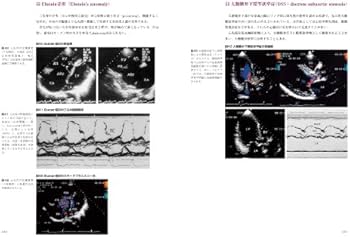

表紙カバーはありませんが、内部に書き込み等はなく、比較的状態良好です。即購入可です。お値下げも対応いたします!お気軽にコメントしてください。- タイトル: 心臓超音波診断アトラス 小児・胎児編 改訂版- 著者: 星見元義- シリーズ: Atlas Series 超音波編 VOL.5 #小児 #エコー #心エコー #小児エコー #先天性心疾患 #先天心 #心臓 #循環器